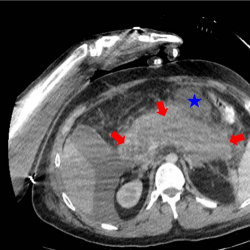

The subjects were categorized into two groups (patient and healthy control groups) based on the presence of acute pancreatitis diagnosis on admission. The studied patient for an algorithm establishment was a 28-year-old male with severe acute pancreatitis who was admitted to the ER less than 24 hours after the symptoms started. The diagnosis was confirmed by clinical examination and by ultrasound examination. The patient’s condition became unstable, and he was transferred to the Intensive Care Unit (ICU), where a CT scan (Fig. 2) and CEUS were simultaneously performed.

infor453_g002.jpg

Fig. 2

28 years old male with severe acute pancreatitis. Contrast-enhanced CT (portovenous phase, the same axial plane as on CEUS image) confirmed acute necrotizing pancreatitis (arrows) with acute necrotic collection (star).